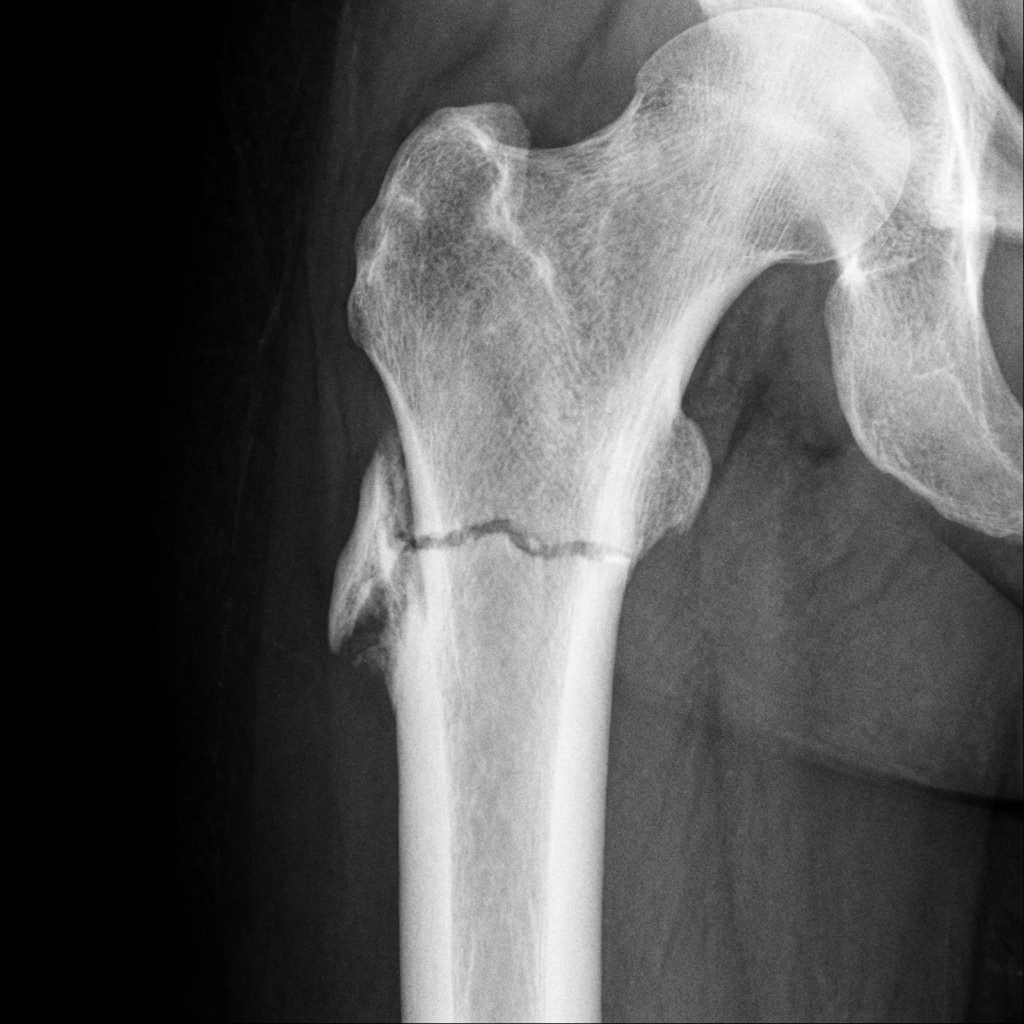

AP radiograph of the proximal femur showing transverse subtrochanteric fracture with classic atypical features: lateral cortical beaking (spike), localized periosteal/endosteal thickening, minimal comminution, and transverse orientation. Note the medial cortical thickening representing stress reaction.

Image source: Open Access medical literature (NIH/PubMed Central) • CC-BY License